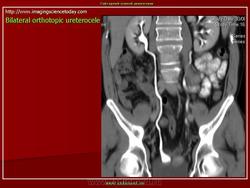

Уретероцеле

Приложения: